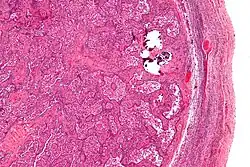

Gonadoblastomas are precancerous lesions that predominantly form in intersex people with gonadal dysgenesis and a Y chromosome.[42][43] This includes conditions such as Swyer syndrome or Turner syndrome with Y chromosome mosaicism.[44][42] These cancer risks are addressed using genetic screening and performing a gonadectomy if necessary.[42]

Micrograph of gonadoblastoma

Image of gonadoblastoma at low magnification

The undescended testes of those with androgen insensitivity syndrome also pose a cancer risk. Those with complete androgen insensitivity syndrome have a 3.6 percent chance of developing a malignant tumor by age 25 and a 33 percent chance by age 50, though malignancy before adulthood is rare.[42][45] Partial androgen insensitivity syndrome poses a higher cancer risks if undescended testes are present.[45] The risk for germ cell tumors from undescended testes is 15 to 50 percent, but the risk for testes surgically moved to the scrotum is unknown.[42] Orchiectomy, removal of the testes, is a preventative treatment option for these cancer risks.[45] For those raised male with partial androgen insensitivity syndrome, a procedure to put the testes into the scrotum called an orchiopexy is done to lower the risk of malignancy.[45]